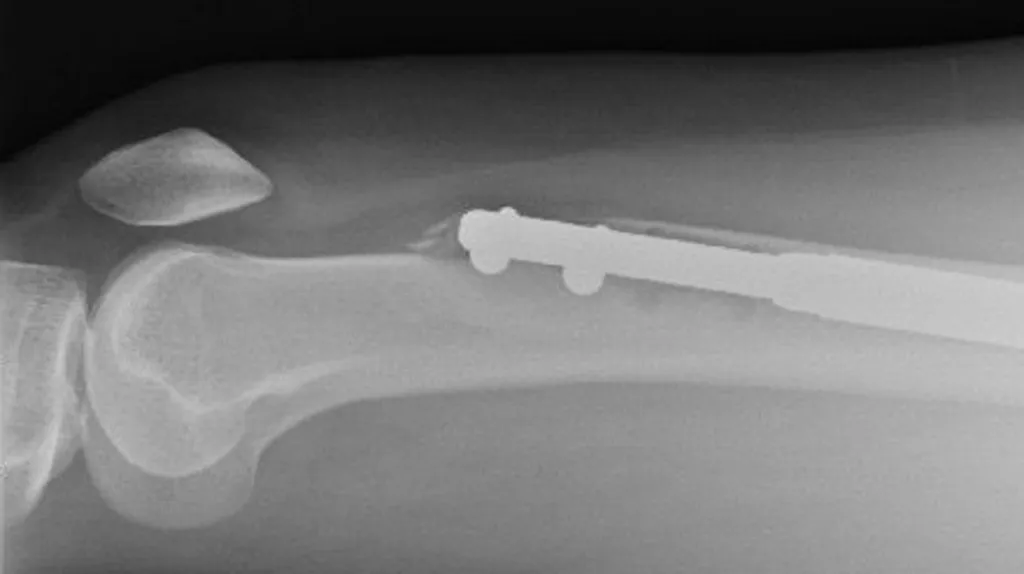

После операции начались проблемы: в её левой ноге сломался металлический стержень, а правая нога не показала должного роста кости. Ей потребовались дополнительные операции, которые стоили ещё больше денег. В итоге, Элейн осталась с серьёзными проблемами с подвижностью и посттравматическим стрессовым расстройством.